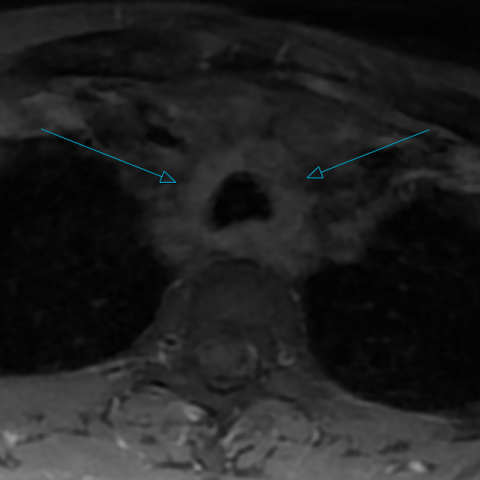

胸腹部增强CT显示气管和主支气管弥漫性环周壁增厚,伴气管周围软组织轻度反应性改变及多发淋巴结肿大(图1)。

1. 胸部、冠状(a)和轴向(b)平面的增强CT显示气管和支气管壁弥漫性增厚,后膜壁结构保留